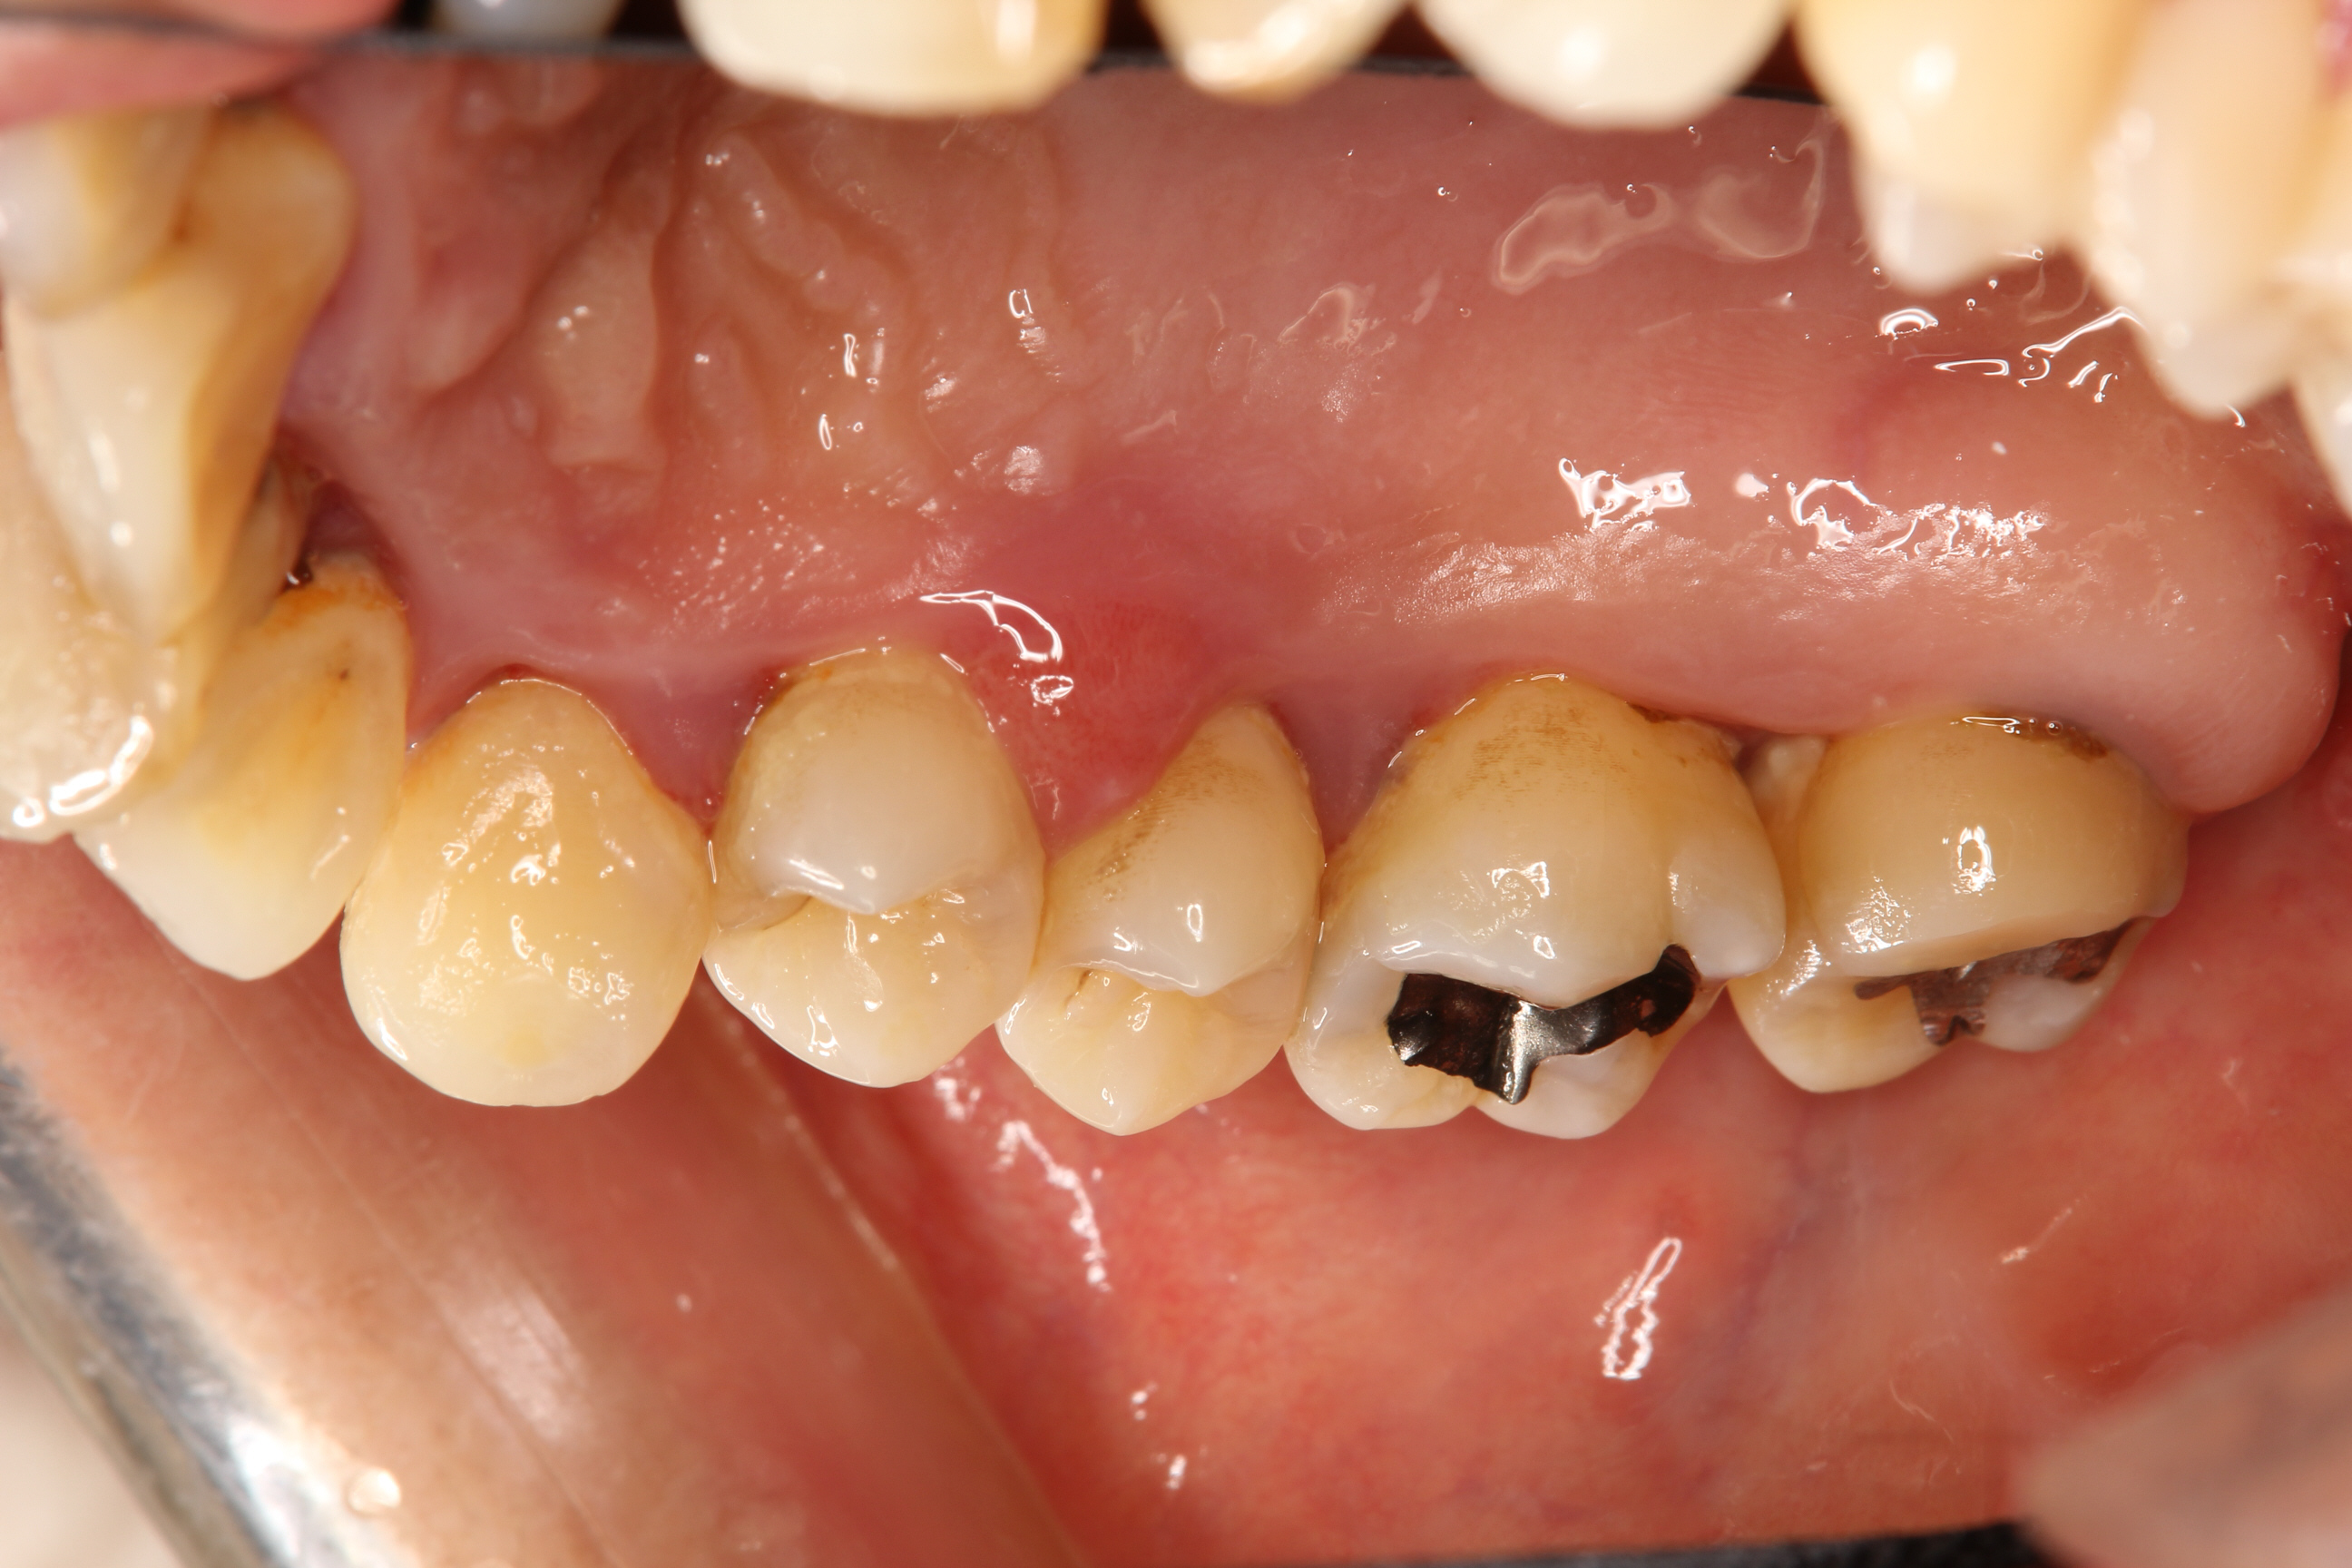

写真の患者さんは、歯周病治療を希望され来院された方ですが、先月全顎的な治療が終わり、メインテナンスに入ることができました。

写真は初診時に撮影したものの一部ですが、全体的に歯肉の炎症が強く、特に口蓋側(歯の内側)の歯肉の腫れが著しく認められます。

歯周ポケットの深さは、ほとんどの歯が7mm以上であり、中には12mmを示す部位もありました。

歯の動揺(揺れ)も2度(中等度)以上を示す部位を多数認めました。